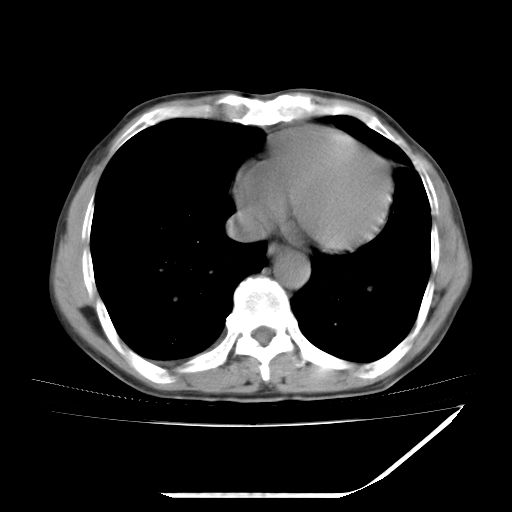

男,59岁,“结核性胸膜炎”30余年,胸部经常疼痛,多次x检查提示“肺部”炎症。腹部疼痛5日,b超提示:“肝内短管结石,余显示不清,建议进一步检查。”

两肺结核并右侧胸腔积液;脾脏、腹腔及腹膜后淋巴结结核[陈旧性];肝内胆管结石

胸部腹部都是结核(双肺。纵隔淋巴结,肝脏,脾脏,肠系膜)

两肺结核并右侧胸腔积液;脾脏、腹腔及腹膜后淋巴结结核[陈旧性];肝内胆管结石。直肠息肉?